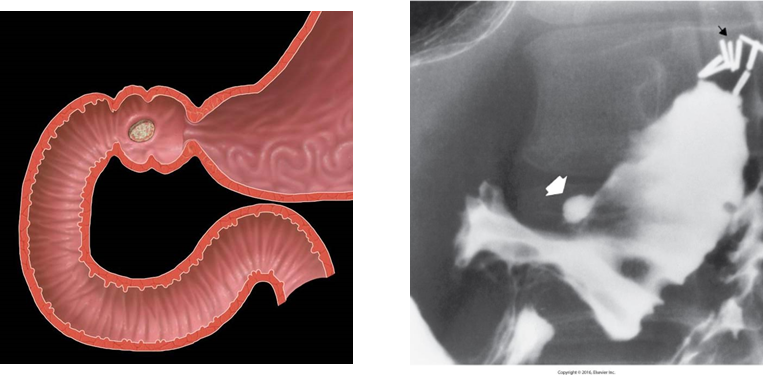

Intussusception

is the telescoping of one part of the intestinal tract into another because of peristalsis.

It forces the proximal segment of bowel to move distally within the outer portion.

Progresses forward causing increased obstruction.

Can compromise the vascular supply and produce ischemic necrosis of the intussuscepted bowel.

Common in ileocolic (ileum and colon) (ileocecal valve – ileum opens in to large intestine) region.

More common in children.

Radiological Appearance

Coiled-spring appearance of barium trapped between the intussusceptum and surrounding bowel.

A bowel obstruction (and therefore air-fluid levels and bowel dilation) proximal to it. There may be an absence of gas in the distal collapsed bowel.